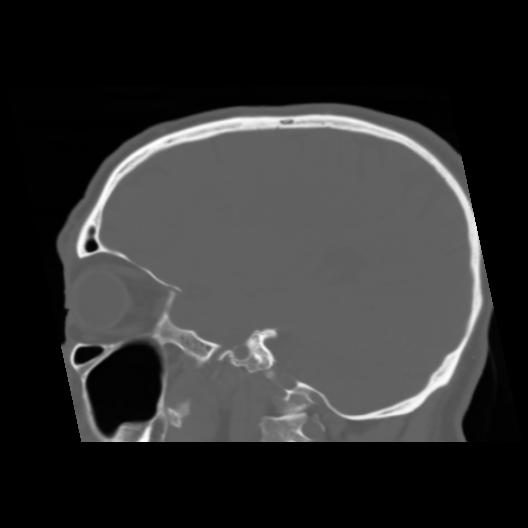

6 CEREBRO,,Sagittal,3.000,CEREBRO,Sagittal,